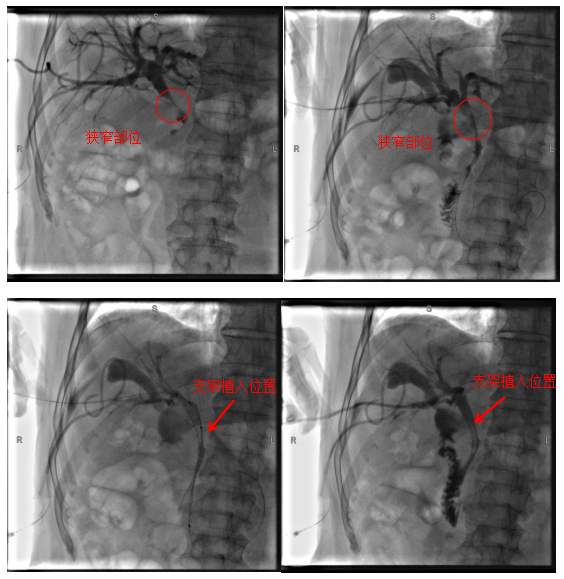

病例2

患者為72歲老年男性,因“右上腹疼痛2月,眼黃、尿黃1周”入院。入院后完善相關檢查考慮膽管中段惡性腫瘤、梗阻性黃疸,患者心肺功能極差,心血管內科、呼吸與危重癥醫學科及麻醉科會診評估后考慮患者無法耐受全身麻醉,肝膽胰外科團隊充分評估后決定為患者行經皮經肝膽道支架植入術,手術順利,術后患者黃疸逐漸消退,有效地改善了患者的生活質量,延長了患者的生存時間。

術中影像